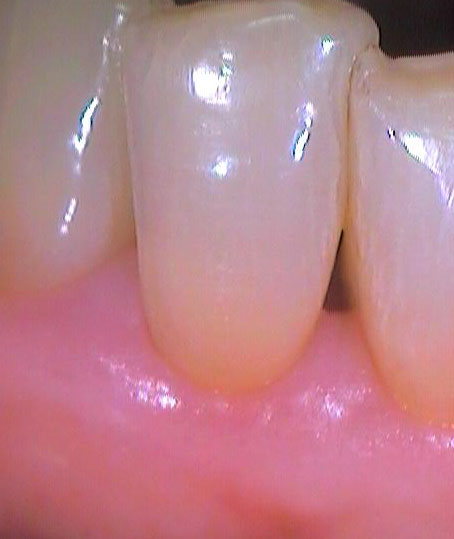

Втори случай

Преди почистване на зъбния камък